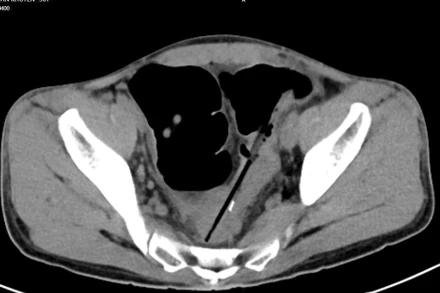

Trung tâm Phẫu thuật tiêu hóa, Bệnh viện Bạch Mai vừa phẫu thuật một trường hợp người bệnh nuốt nhiều dị vật gây biến chứng thủng đại tràng.

Sáng 17-1, Đại tá Nguyễn Quốc Dũng, Phó Chủ nhiệm khoa Ngoại bụng, Bệnh viện Quân y 175 (Bộ Quốc phòng) cho biết, bệnh viện vừa phẫu thuật cấp cứu một trường hợp nuốt dị vật trong bụng.